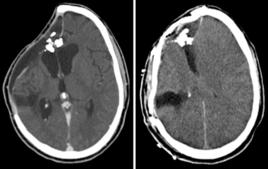

⒉手術因素:體外循環下心臟直視手術的術後急性精神障礙發生率遠較其它手術高,主要原因是體外循環可能導致的腦栓塞或腦的低灌注。此外,神經外科手術、創傷較大的胸腹部手術及髖關節置換術術後精神障礙發生率也較高。

⒋圍術期管理:術中血壓波動過劇、低氧血症、過度通氣、失血或極度血液稀釋影響腦血流和腦供氧,對術後精神障礙有直接或間接的影響。此外,術後疼痛及睡眠周期的改變也是術後急性精神障礙的誘因。